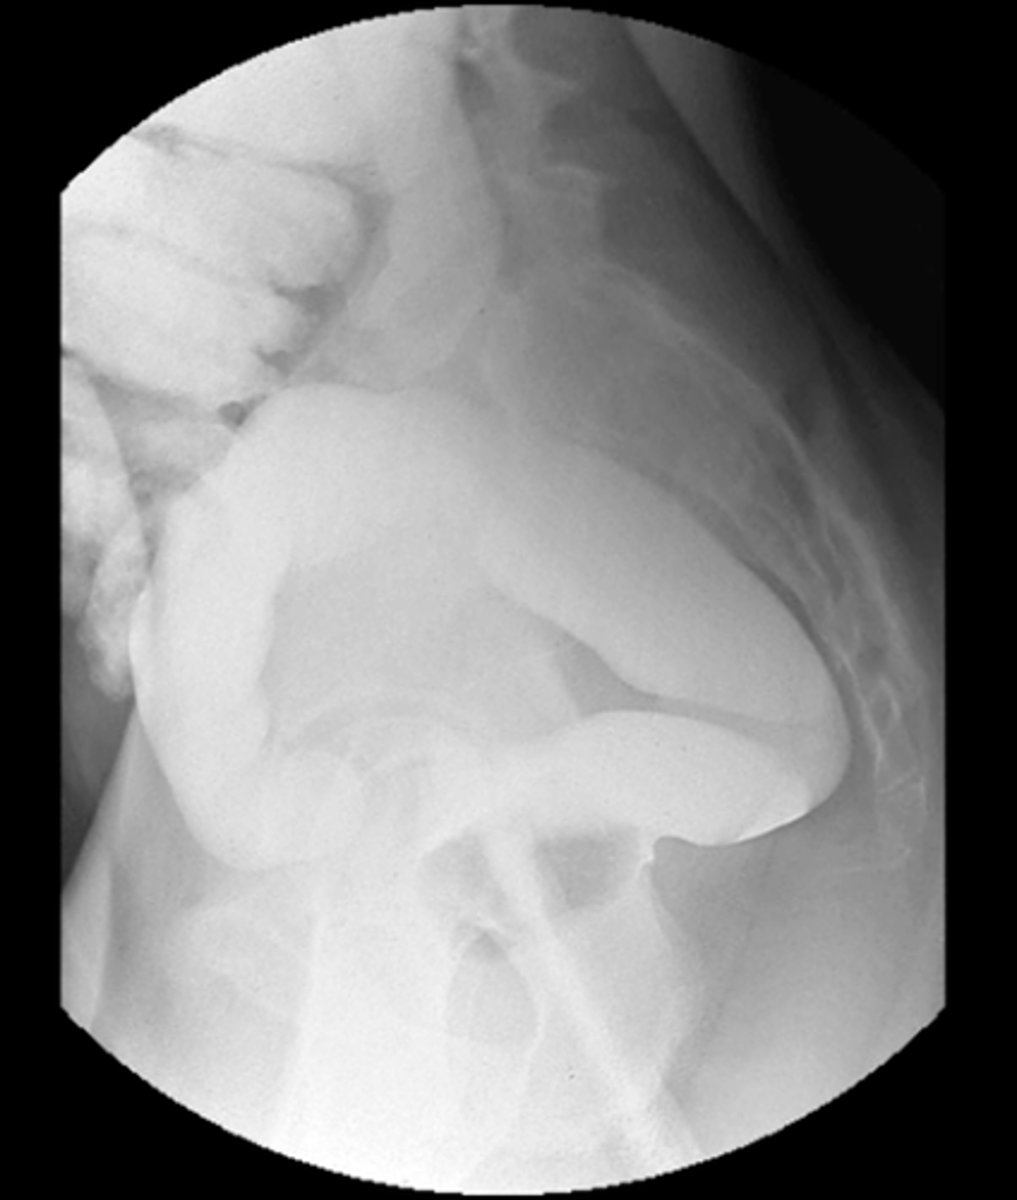

Intravenous pyelogram (IVP)

What is the image?

Lateral rectum with barium enema

Rectal tube

What is indicated in the image?

Rectum

Voiding cystourethrogram

Bladder

Membranous urethra

Prostatic urethra

Spongy urethra